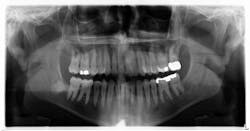

A healthy, 38-year-old male presented to the office for a comprehensive exam. His blood pressure was within normal limits, and no medications were being taken. Bitewing radiographs were taken, and it was noted that there was a cystlike lesion on what appeared to be a mesial impaction of no. 17. A panoramic radiograph indeed revealed a large, radiolucent/cystlike lesion surrounding a mesial/inferior-positioned no. 17. The widest point of the cyst measured approximately 3 cm. The patient reported knowing about the lesion but was not inclined to have it removed because it was not bothering him. The area was not tender to palpation; tooth no. 18 had normal pocketing and tested normal to cold, percussion, and bite.